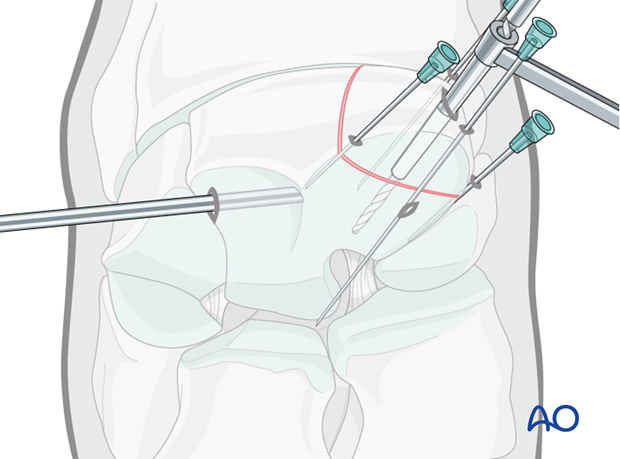

Based on the radiographs a stab incision is placed over the dorsal aspect of the third carpal bone half way between the spinal needle and the needle in the carpometacarpal joint.

The glide hole is drilled across the fragment until it enters the fracture line (the distance is predetermined by measurement by the radiographs).

The drill depth can be verified using an intraoperative radiograph.